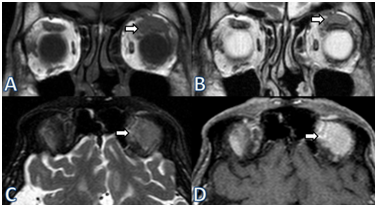

An 86-year-old man presented with a two week history of unilateral ptosis and erythema of the upper eyelid (Figure 1). On examination, the best corrected visual acuity was 20/40 in both eyes. Anterior segment biomicroscopy of the left eye showed a diffuse, slightly elevated, fleshy mass at mid-bulbar conjunctiva hidden by upper eyelid and bilateral nuclear cataracts (Figure 2). The marginal reflex distance of the right eye was 5mm, while it was 2 mm on the left side. No proptosis was detected. The orbital magnetic resonance imaging (MRI) showed 18x8x20 mm lesion with unclear margins, between levator palpebra superior and superior rectus muscle in the left orbit (Figure 3). Right eye, which had no pathological findings during the examination, also had a 14x8x8.5 mm lesion located near central of the lateral rectus of the right eye (Figure 4). Excisional biopsy was performed to the conjunctival mass and sent for histopathological analysis (Figure 5). Atypic lymphocytes with diffuse infiltration and plasma cells with positive CD20, MUM-1, Bcl-2 immunohistochemistry staining and a Ki-67 labeling of 40% were observed (Figure 6). Systemic work up including PET scan showed the involvement of bilateral cervical lymphoid chains, abdominal paraaortic lymphatic nodes and the right lung. Immediate chemotherapy was initiated, however the patient only survived for two more months after the diagnosis.

Figure 3 Left orbital MRI showing 18x8x20 mm isointense lesion with unclear margins, between levator palpebra superior and superior rectus muscle in the left intraconal space (A), minimal hyper intensity at coronal T2-weighted images (B), isointense in fat suppressed T2-weighted imaging (C), opaque lobule after IV contrast injection (D).